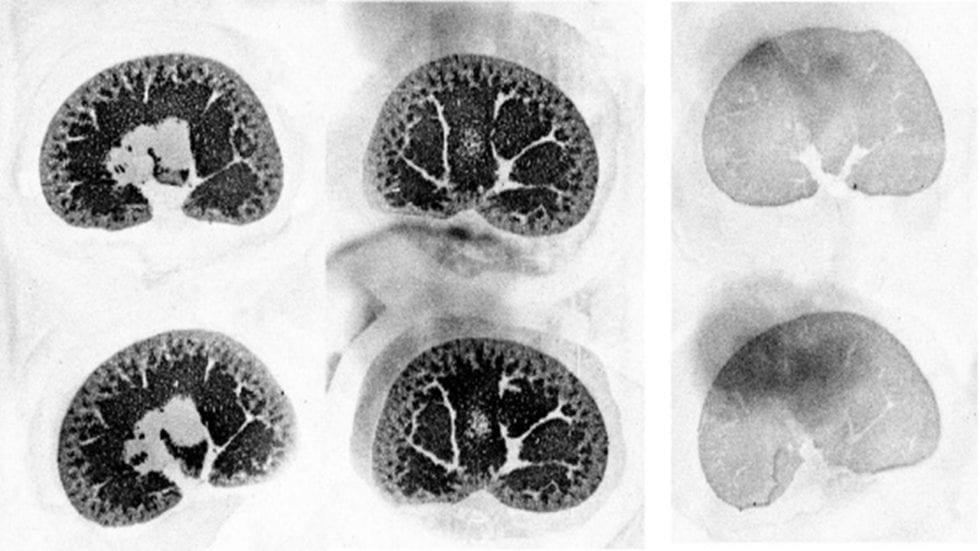

Figure 1 from Receptor autoradiography in thoracic spinal cord Receptor Autoradiography Neurons Despite its development almost 40 years ago, receptor autoradiography remains a regular and reliable practice for the localization. For cell and tissue localization of drugs, receptor microscopic autoradiography is reviewed, including its development history,. How receptor systems are situated within macro. Neurotransmitter receptors support the propagation of signals in the human brain. The combination of in situ hybridization and receptor. Receptor Autoradiography Neurons.

Figure 1 from Receptor autoradiography in thoracic spinal cord Receptor Autoradiography Neurons For cell and tissue localization of drugs, receptor microscopic autoradiography is reviewed, including its development history,. Despite its development almost 40 years ago, receptor autoradiography remains a regular and reliable practice for the localization. The combination of in situ hybridization and receptor autoradiography/immunohistochemistry allows. In this study, we used in vitro receptor autoradiography to measure the density of 14 neurotransmitter. Receptor Autoradiography Neurons.